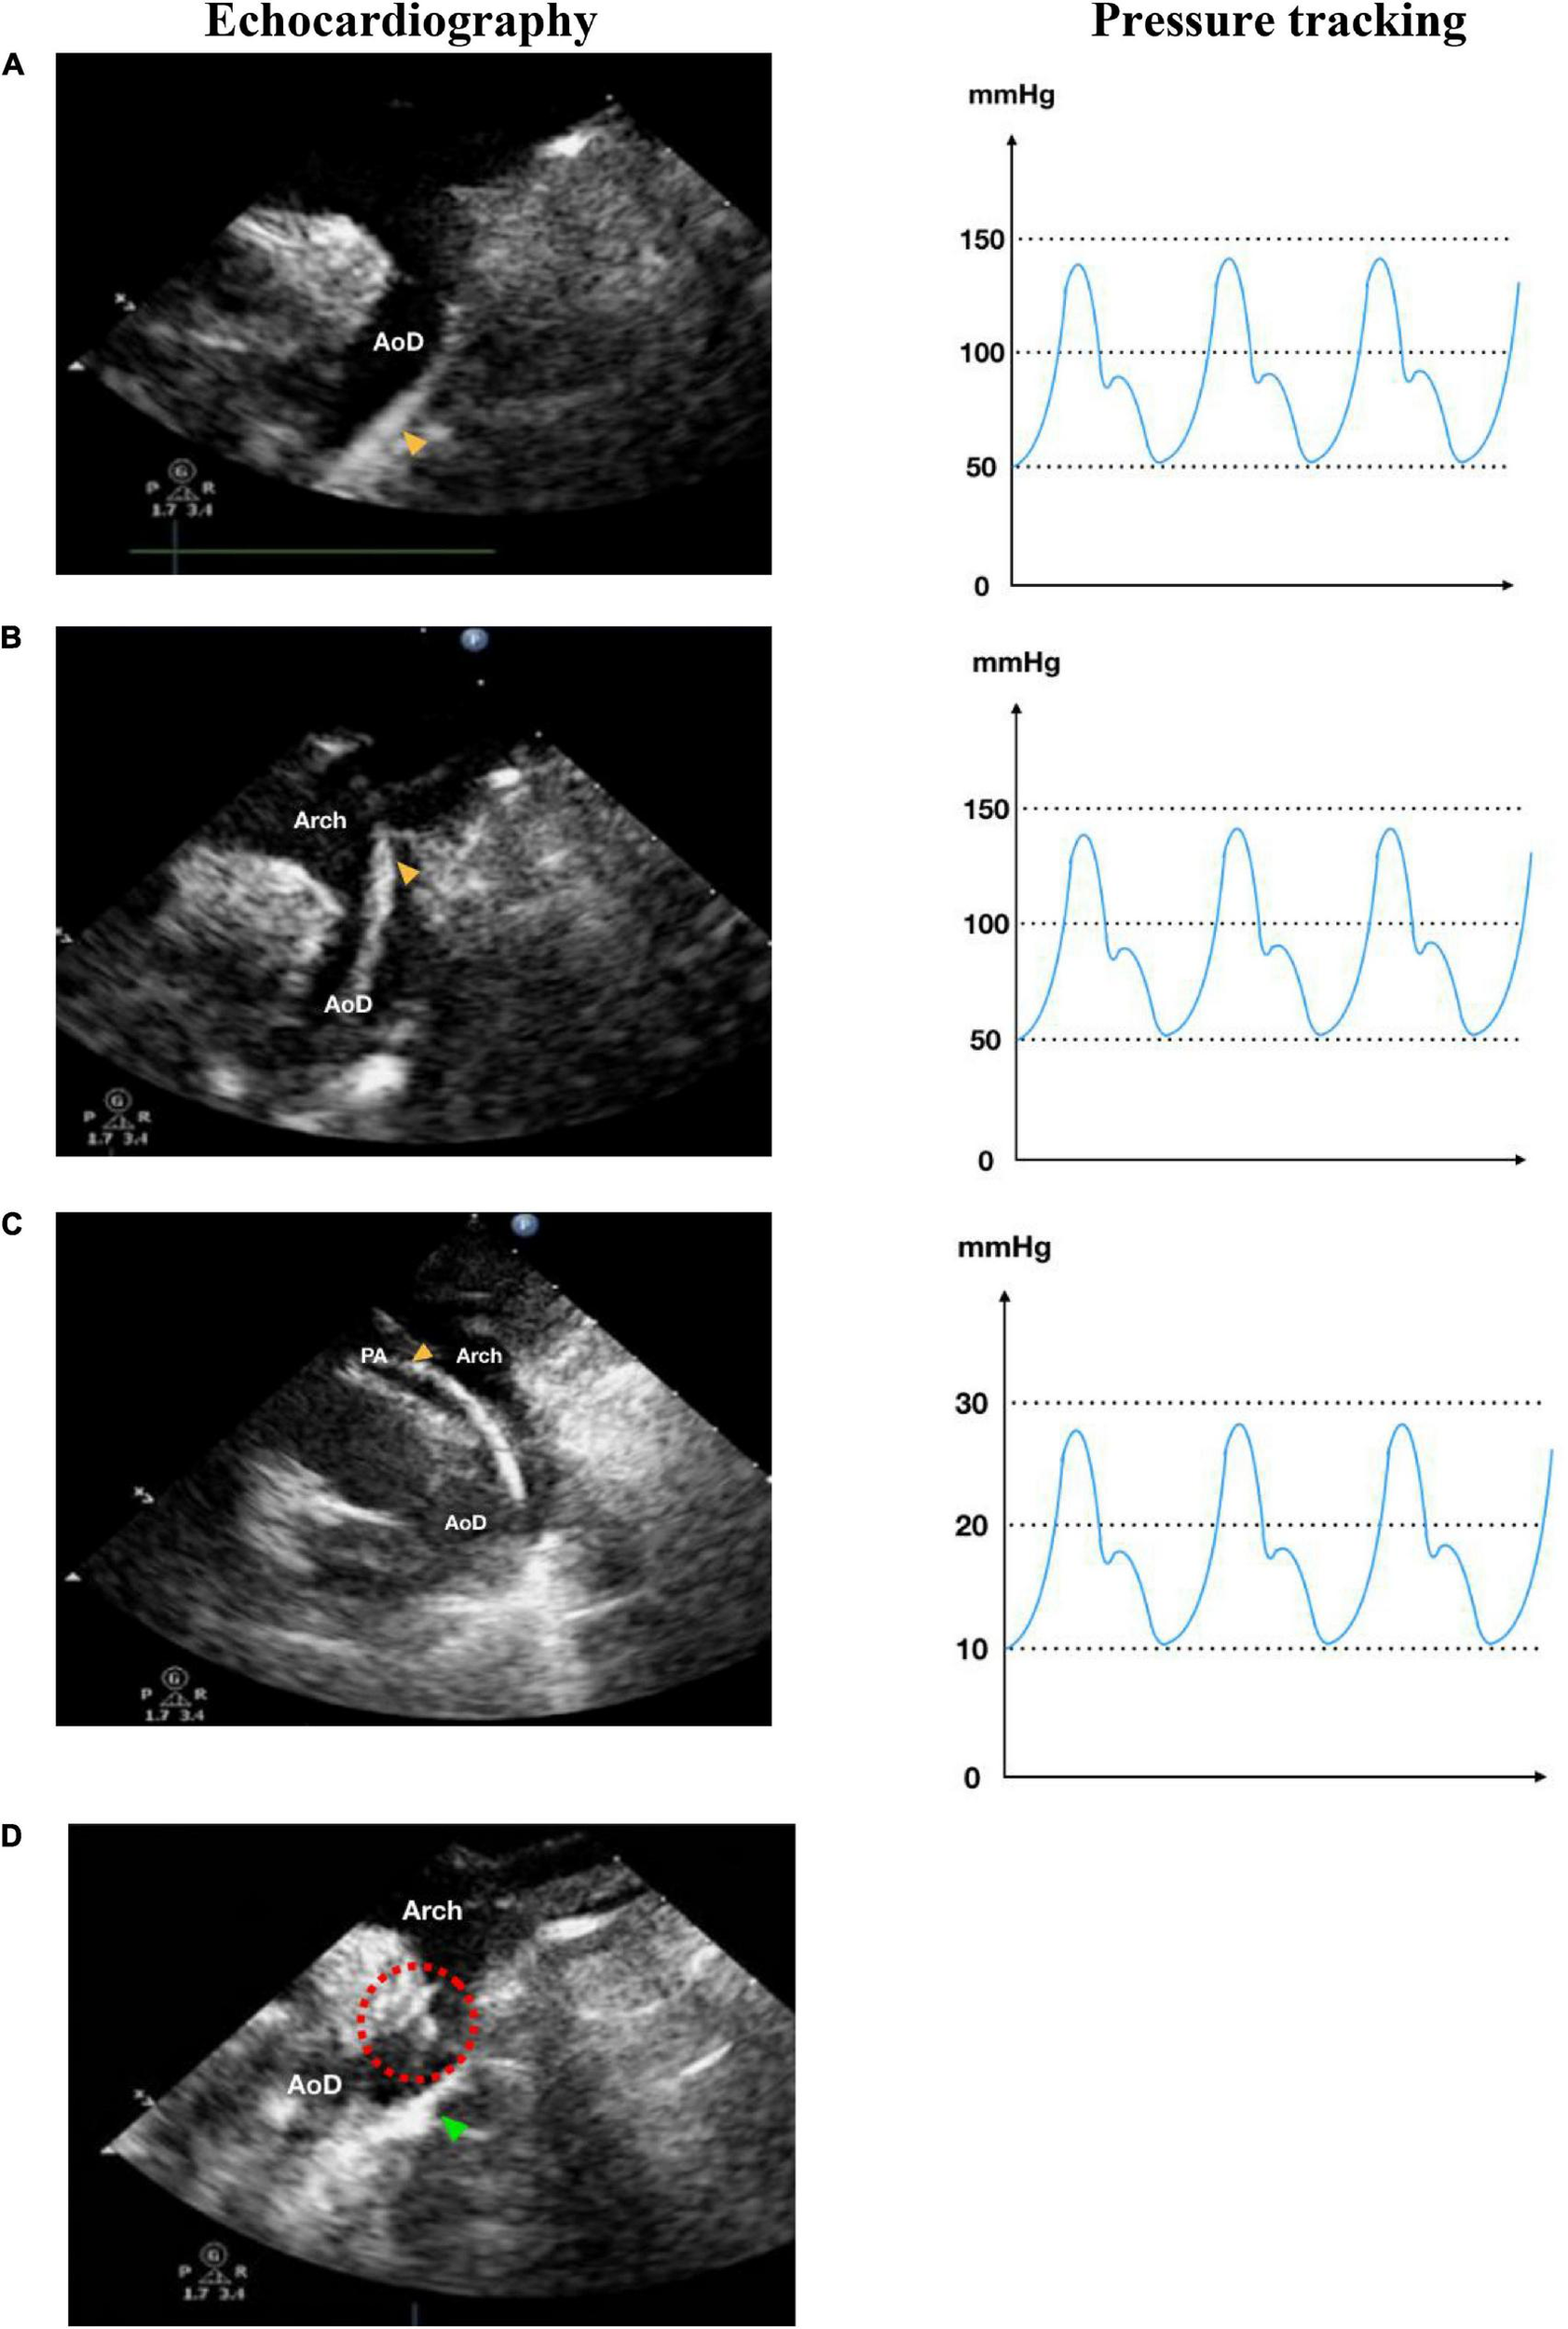

FIGURE 3

Retrograde transarterial approach of percutaneous patent ductus arteriosus (PDA) closure. (A) Catheter is seen in AoD in TTE arch view. (B) Catheter is pushed towards the aortic arch in TTE arch view. (C) In parasternal short axis TTE view as high as the great arteries, the catheter is seen in PA through PDA from AoD. (D) In TTE arch view, the device is stowed in place (shown by red dotted circle) after being delivered from the delivery cable. IVC, inferior vena cava; RA, right atrium; RV, right ventricle; PA, pulmonary artery; Ao, aorta; LA, left atrium; LV, left ventricle; AoD, descending aorta; PDA, patent ductus arteriosus. Orange arrowhead shows the catheter head. Green arrowhead indicates the occluder device.

In this study, we compared the time taken for PDA closure procedures using fluoroscopy and echocardiography. The median procedural time of using both antegrade and retrograde approaches for the test and control groups was insignificant (p = 0.575). The retrograde approach had a shorter procedural time in comparison to the antegrade approach where the catheter needs more manipulation to be directed into the right ventricle and PA to reach the PDA (see Figures 2C,D). However, the retrograde approach is limited to patients with low body weight or large PDA since complications might occur through arterial access, such as thrombosis at the access site. Regardless of the approach, the difference in procedural time between the echocardiography group and the fluoroscopy group was insignificant (p = 0.09). These results mean that using only echocardiography did not compromise procedural time.